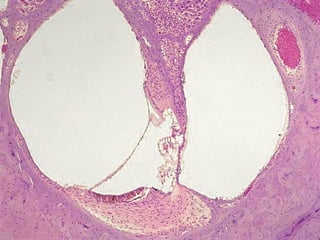

Utrículo

Macula del

Saculo